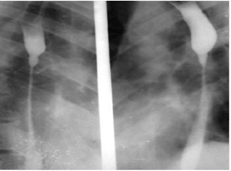

При контрольной эзофагоскопии (рис. 2) и рентгеноконтрастном исследовании пищевода (рис. 1) выявлены признаки формирующегося рубцового стеноза: сужение просвета на участке прежнего ожога, замедленное прохождение контраста через поражённый сегмент, локальное нарушение растяжимости стенки.

Рис. 1. Стеноз пищевода на рентгенографии

Дополнительно выполнялось рентгеноконтрастное исследование пищевода с оценкой проходимости, локализации и протяжённости сужения. Лечение проводилось в условиях многопрофильного стационара и включало интенсивную терапию в остром периоде, нутритивную поддержку с последующим наложением гастростомы, а также курс последовательных эндоскопических расширений пищевода.